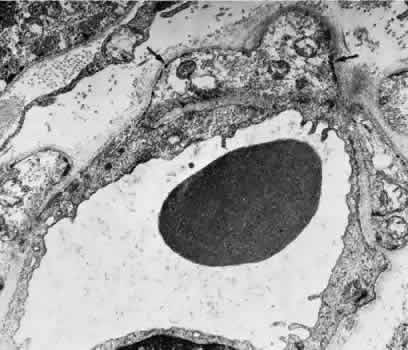

With aging, the connective tissue adjacent toand surrounding the choriocapillaris undergoeschanges, and electron-dense filaments and wide-spacing collagen may be seen. The main nerve supply to the choroid is from the ciliary nerves. A significant proportion of the fibers innervate the blood vessels and belong to the sympathetic nervous system. Delicate plexuses and ganglion cells are found in the surrounding connective tissue, and unmyelinated fibers course toward the vessel wall.62 CILIARY BODY AND IRIS The arterial blood supply to the ciliary body is from the branches of the long PCA, branches of the anterior ciliary arteries, and branches from the major arterial circle. Funk and Rohen,63 using scanning electron microscopy of resin casts of the ciliary body and iris vessels, have contributed significantly to our understanding of the anatomy of these vessels. They found that the perforating branches of the anterior ciliary arteries form an intramuscular circle that supplies the outer and posterior portions of the ciliary muscle, the iris, and the anterior choroid. The major circle of the iris is located more anteriorly and is supplied by the long PCAs and branches from the anterior ciliary arteries. The iridic major circle contributes to the anterior supply of the ciliary body as well as to the iris and ciliary processes. The ciliary processes themselves have three distinct vascular territories, each with its own system of arterioles and venules.63 The small arteries of the stroma of the ciliary body contain an endothelium and basement membrane, a poorly developed elastic lamina, a media containing two or three layers of smooth muscle, and a loose collagenous adventitia. Most ciliary vessels drain posteriorly into the choroidal and vortex systems. The remaining drainage is into the intrascleral venous plexus and the episcleral veins of the limbal region. Small veins and venules are found in the ciliary processes along with the capillaries. These vessels are often closely apposed to the pigmented layer of the epithelium surrounding the ciliary processes. The capillaries and venules of the ciliary body are 15 to 30 μm in diameter and are fenestrated in both the pars plicata and pars plana. They closely resemble the capillaries of the choriocapillaris except that they are smaller. The fenestrae of these vessels range in size from 300 to 1,000 nm in diameter.64 The major difference between the capillaries in different areas of the ciliary body is that only those of the pars plana are in contact with the elastica of Bruch's membrane on the surface facing the pigmented epithelium. The capillaries present in the ciliary muscle are nonfenestrated (Figs. 16 and 17). The blood vessels are innervated by small branches of sympathetic fibers. The iris blood vessels derive from the major iridic arterial circle and drain into the vortex system. The blood vessels of the iris are believed to have a slight corkscrew shape so they can accommodate to the changes in the length of the iris during dilation and contraction. A striking finding in all the iris vessels is the presence of thick collagenous adventitia that is several microns thick. There are approximately 200 radial vessels in the iris. The density of these vessels is greater than expected for the nutrition of the iris, and they probably account for anterior-segment thermal homeostasis and provide a high oxygen content for the corneal endothelium. Most of the vessels in the iris stoma are arterioles (Figs. 18, 19, and 20), venules, and capillaries (Fig. 21). The capillaries have unfenestrated endothelium with tight junctions. The main branches of these radial vessels form an incomplete circular arterial ring at the collarette (minor iris circle). Branches from the minor circle extend into the pupillary region to form capillary arcades. The venous drainage system parallels the arterial inflow pattern. The radial arteries of the iris are truly arterioles, with an overall diameter of 15 to 50 μm. The radial iridial veins are technically pericytic venules. They are approximately 30 to 90 μm in diameter. The media consists of one or two layers of pericytes. These cells make frequent contact with the endothelial cells but not with each other.